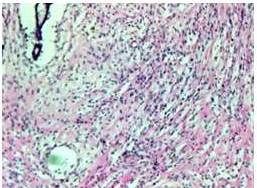

aciente femenina de 46 años, quien inicia enfermedad actual en 2014, cuando presenta aumento de volumen progresivo en mama izquierda, de 6 meses de evolución, al examen físico se observa un tumor sólido, blando, no adherido a planos profundos, móvil, que abarca la totalidad de la mama, de 30 cm x 30 cm, adenopatías axilares múltiples móviles, blandas, el examen ecosonográfico demuestra una imagen nodular sólida de gran tamaño 28 cm x 27 cm, hipoecoica, de contornos definidos, en la mamografía, mamas densas, se observan calcificaciones gruesas dispersas. La mama derecha era voluminosa, sin signos aparentes de lesiones. Se realizó una biopsia por aguja gruesa (BAG) con el hallazgo histológico de proliferación de componente mesenquimal y epitelial concluyendo como tumor filodes. Se realizó una mastectomía simple izquierda, evidenciando tumor de 20 cm x 20 cm que ocupa toda la mama izquierda, con red venosa en relieve con la piel; cuya evaluación histológica reportó un tumor filodes benigno (Figura 1-4) con bordes de resección negativos con márgenes amplios; la paciente continua en control, evidenciándose en el año 2016 una lesión tumoral en cuadrante superior interno (CSI) de la mama derecha, de 4 cm x3 cm, móvil, no doloroso, se solicitó ecografía y mamografía para evaluar la nueva lesión, sin embargo, la paciente se ausenta. Consulta de nuevo en 2017, al examen físico el tumor abarcaba la totalidad de la mama, de 20 cm x 23 cm, móvil no doloroso, con mama supernumeraria ipsilateral (Figura 5). En la mamografía, mama densa, se observaron calcificaciones gruesas dispersas, se realiza BAG con el diagnóstico de tumor estromal y epitelial (tumor bifásico); se realizó una mastectomía simple con resección de la mama supernumeraria, el diagnóstico definitivo fue tumor filodes borderline (Figura 6 - 8). Actualmente la paciente no presenta signos de enfermedad.

Macroscópicamente, los tumores más pequeños semejan fibroadenomas con un aspecto fibroso gris y blanco, mientras que los más grandes semejan sarcomas. Histológicamente se asemejan a elementos epiteliales y del mesenquima de un fibroadenoma, pero se diferencia por el potencial de crecimiento y celularidad del estroma (6,7,8).

Este tumor por su naturaleza, crece radialmente, comprime el parénquima mamario y crea una pseudocápsula a través de la cual sobresalen lengüetas. El examen del tejido conectivo en secciones múltiples es obligatorio, porque el filodes maligno puede estar presente solamente en una porción del tumor (6).

El diagnóstico diferencial debe establecerse con el fibroadenoma mediante criterios morfológicos. El tumor filodes benigno se caracteriza por una marcada hipercelularidad estromal y el maligno por una malignización del estroma con cambios metaplásicos (3,4).

La Organización Mundial de la Salud (OMS) los clasifica en tumores benignos, borderline, y malignos, según su comportamiento biológico de acuerdo a tres características histológicas: el patrón de crecimiento periférico, si es infiltrativo o expansivo, el índice mitótico del componente mesenquimático y las atipias nucleares.